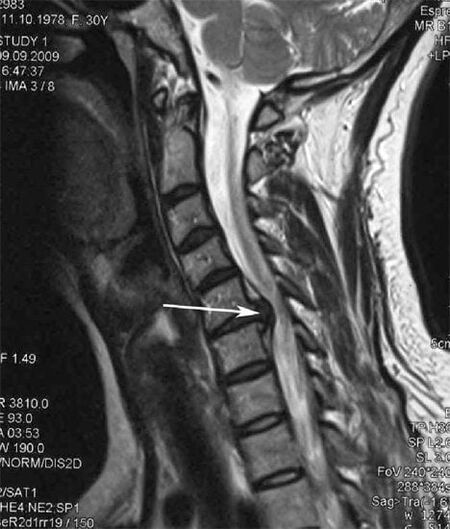

En las etapas iniciales, la osteocondrosis se detecta mediante resonancia magnética.. Posteriormente, la patología se puede diagnosticar mediante radiografía. En las radiografías de la columna cervical se nota una reducción en la distancia entre las vértebras, cambios patológicos en las articulaciones facetarias y osteofitosis.

Muchas personas se quejan de que no pueden girar el cuello debido al dolor intenso que sienten cuando de repente levantan algo pesado. Este fenómeno indica el desarrollo de una hernia de disco. La causa del dolor en la espalda, el cuello y las extremidades superiores es el pellizco de una de las raíces nerviosas que salen de la médula espinal.

La enfermedad se caracteriza por la inflamación de los nervios espinales implicados en la formación del plexo braquial. La causa del proceso inflamatorio puede ser intoxicación aguda, hipotermia, pellizco de una raíz nerviosa por músculos calambres, Hernias intervertebrales u osteofitos..